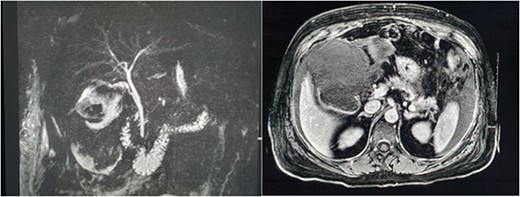

She presented on this occasion with right upper quadrant pain and collapse. Computed tomography (CT) abdomen and pelvis with intravenous contrast in the portal venous phase was performed, demonstrating perforated acute calculous cholecystitis and active haemorrhage (Fig. 1). At this point, Interventional Radiology and Upper gastrointestinal (GI) Surgery in our institution were contacted, and the patient was transferred for emergency embolization. The patient was haemodynamically unstable, so the massive transfusion protocol was commenced.

CT abdomen and pelvis with intravenous contrast in the portal venous phase was performed demonstrating perforated acute calculous cholecystitis and active haemorrhage.